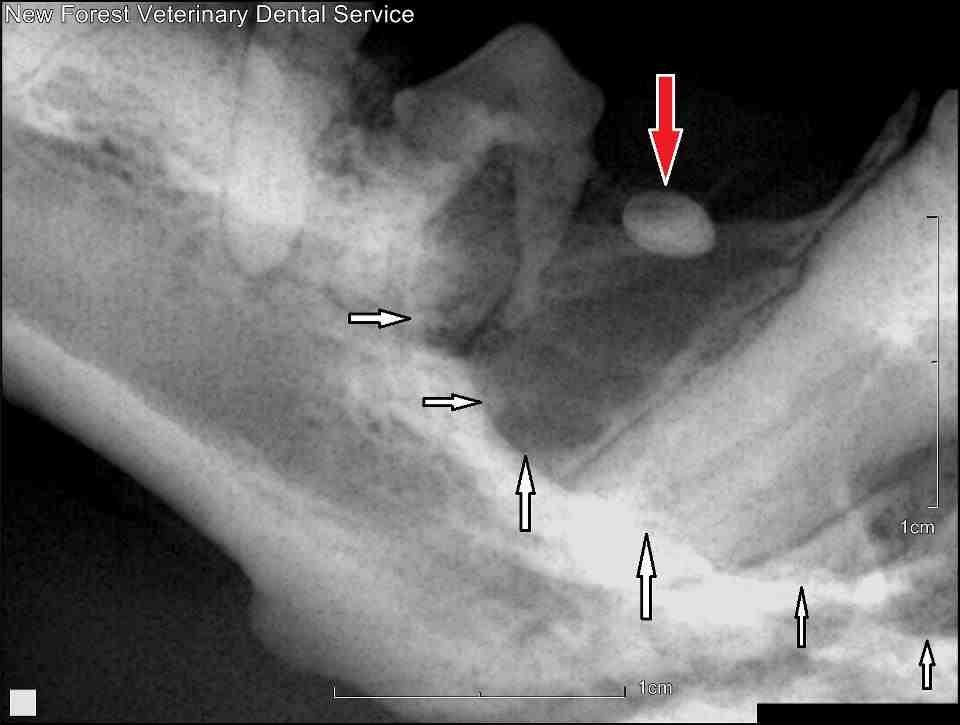

Dentigerous Cysts are lesions that we see as referral cases commonly. They are fluid filled structures present within the jaw and are associated with abnormally erupted teeth. They can grow very large, and in compressing the bone they can be very painful. If not treated, these lesions can go on burst which will then usually result in their infection, or they can even cause fractures of the jaw.

Treatment can be very challenging, and requires the complete removal of the cyst lining. If this isn't done then the cyst can return. Closure of the surgical site can also be challenging owing to the amount of tissue that sometimes needs to be removed.

If you think a patient has a Dentigerous cyst, then we are more than happy to see them for surgery. We would also encourage vets and nurses to check young dogs at neutering procedures, to see if they have any missing teeth. Missing teeth, especially 1st premolar teeth, should be xrayed to see if the tooth is genuinely missing, or if it is unerupted. Extraction at this stage can avoid the development of painful Dentigerous cysts.